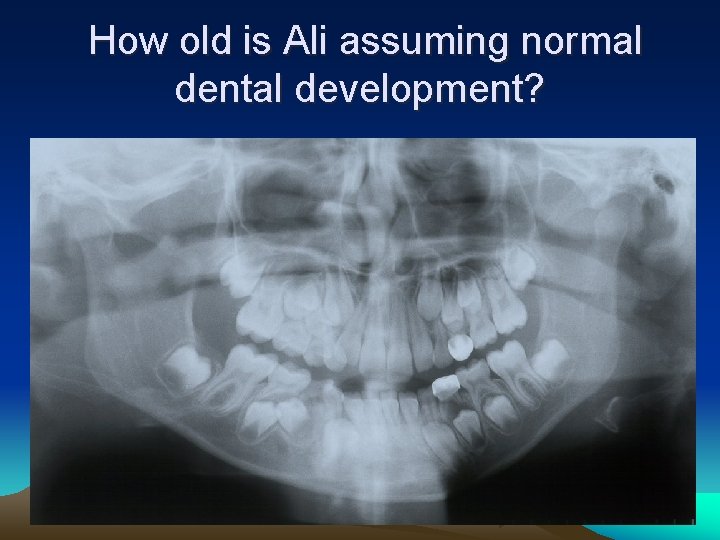

How old is Ali assuming normal dental development?

Assuming normal dental development, Ali is 8 years old.